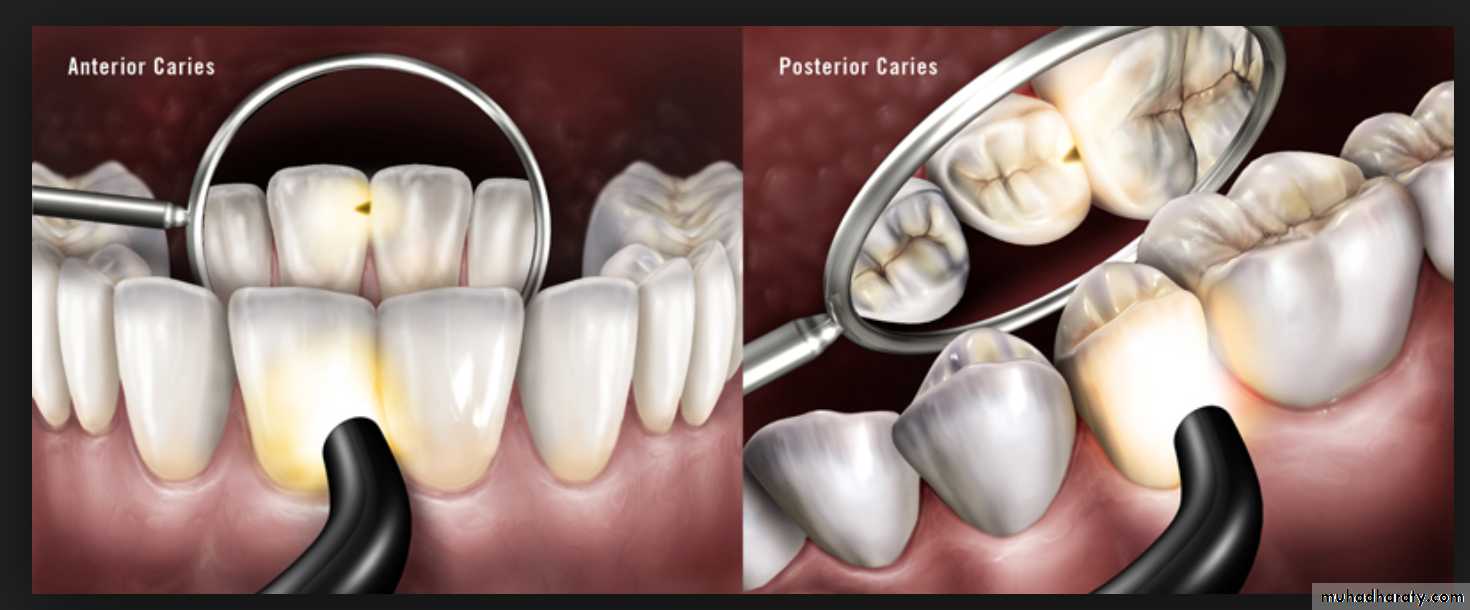

Conventional Methods –Visual examination

Use of visual examination only, is known as the European method, while use of sharp or blunt probe in visual tactile system is popularly known as the American system for diagnosis of dental caries.Visual examination for diagnosing dental caries is a very popular method. It is based on the criteria such as:

Cavitation, surface roughness, opacification and discoloration of clean and dried teeth under adequate light source.

Cavitated Lesions

Where there is visual breakdown of a tooth surface, it is classified as cavitated carious lesion. An active cavity on a smooth surface has soft walls or floors as shown below:Secondary caries